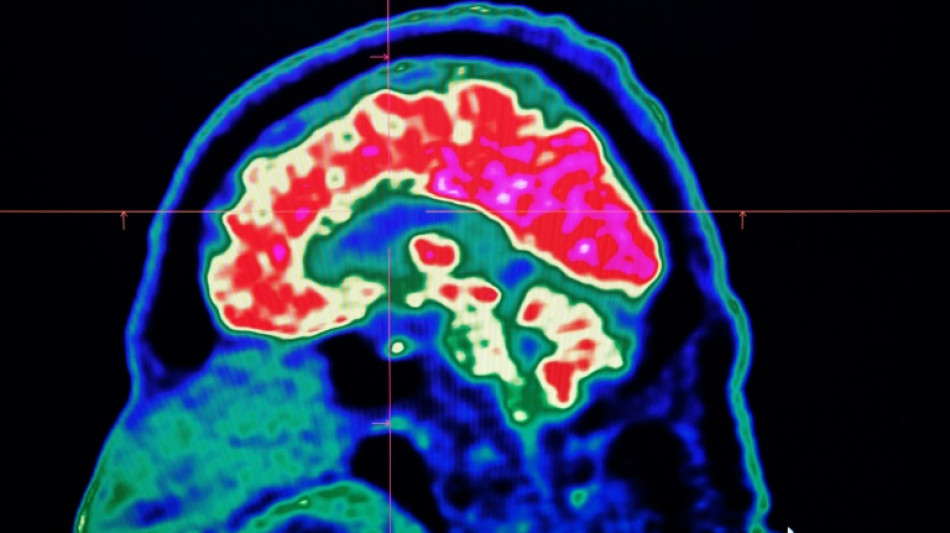

Surging nervous system disorders now top cause of illness: study / Photo: Fred TANNEAU - AFP/File

Conditions affecting the nervous system -- such as strokes, migraines and dementia -- have surged past heart disease to become the leading cause of ill health worldwide, a major new analysis said on Friday.

More than 3.4 billion people -- 43 percent of the global population -- experienced a neurological condition in 2021, far more than had previously been thought, the analysis found.

The researchers looked at how 37 different neurological conditions affected ill health, disability and premature death across 204 countries and territories from 1990 to 2021.

More than 443 million years of healthy life were lost to nervous system disorders globally in 2021, an 18-percent increase from 1990, the study found.